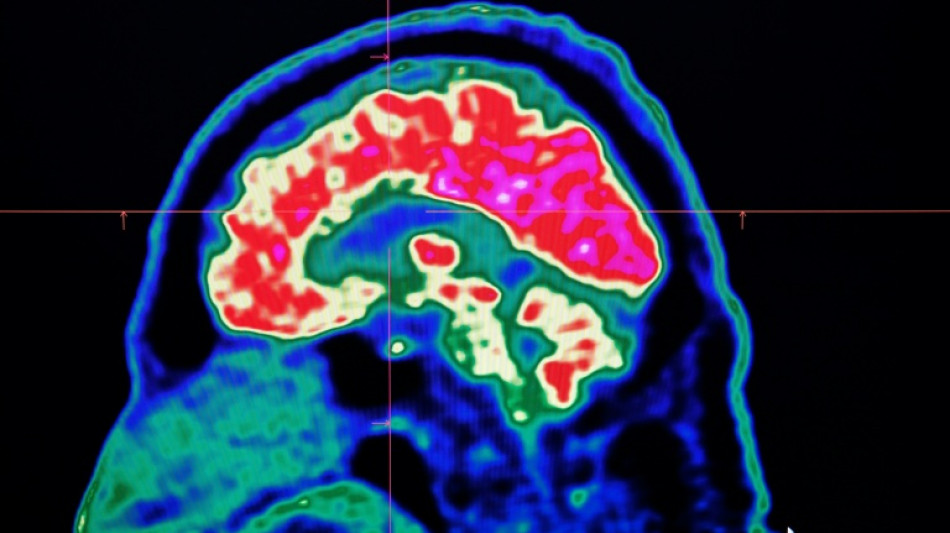

Final report casts doubt on existence of Canada mystery brain illness / Photo: © AFP

In 2021, health officials in New Brunswick launched an investigation involving 48 patients with a range of neurological symptoms but no apparent common illness. These included muscle spasms, memory loss, hallucinations and balance issues.

Some in the province of less than a million people began describing the condition as a mystery brain disease.

Provincial officials said at the time that the patient group could be suffering from a new disease not previously seen in Canada and began using the term "possible neurological syndrome of unknown cause."